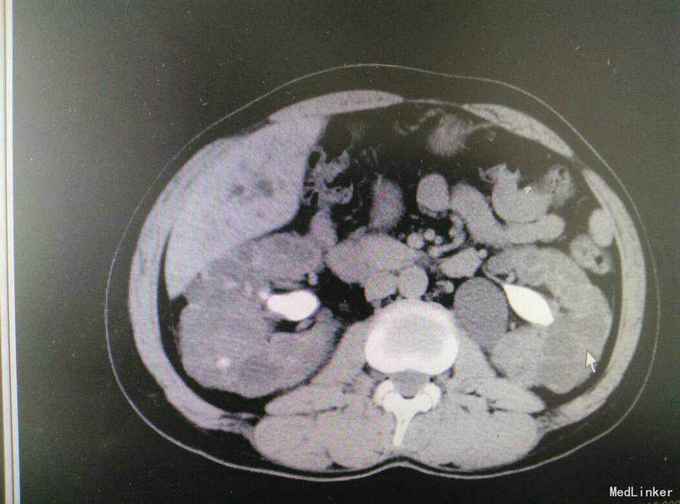

多囊肾合并双肾结石并积水

肾结石 多囊肾 多囊肝

患者47岁,男,因‘’腰痛伴、血尿伴发热7天‘入院。 患者既往有‘高血压’病史多年,7天前无明显诱因出现腰痛,随后出现肉眼血尿,为程肉眼血尿,当天晚上出现发热,最高体温38.6摄氏度,予以对症处理后,发热可退去,但症状反复,患者为求进一步进一步治疗遂来我院。

多囊肾,双肾结石,多囊肝,高血压